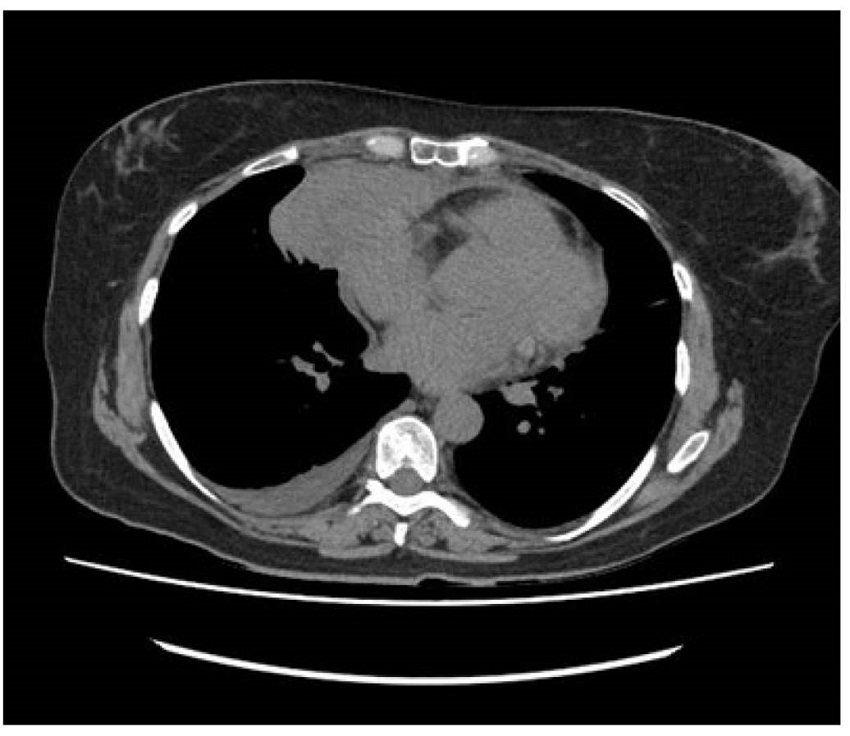

El estudio de imagen se amplió con una tomografía computarizada (TC) torácica, en la que finalmente se constató la presencia de una masa en mediastino anterior de 87 x 56 mm, hipodensa, con calcificación en la parte lateral derecha que condicionaba la zona de atelectasia periférica en el parénquima pulmonar subyacente (figura 3). La paciente ingresó en planta para continuar el estudio y se le hizo una punción con aguja fina (PAAF) y una microbiopsia de la lesión, con diagnóstico anatomopatológico definitivo de timoma, por lo que fue derivada al servicio de cirugía torácica para plantear exéresis quirúrgica. Esta fue realizada con éxito. Posteriormente, la paciente fue evaluada tanto en nuestra consulta como por el servicio de cirugía torácica y comprobamos que no había ningún tipo de complicaciones.